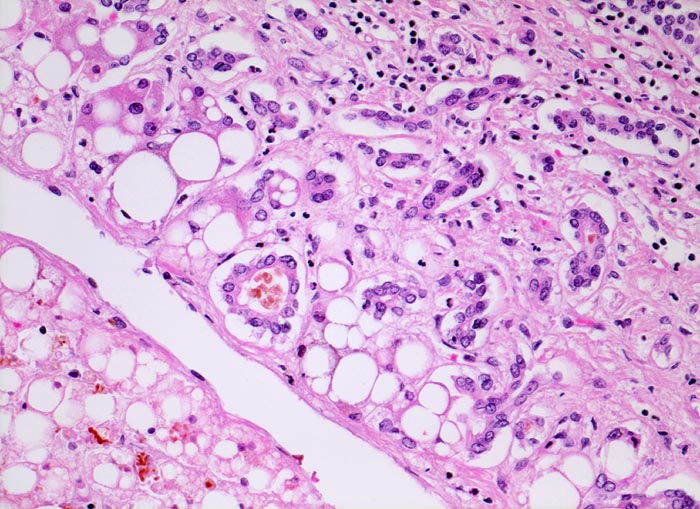

Die Steatose ist der früheste und häufigste pathologische Leberbefund ( 3260) und findet sich bei bis zu 90% der chronischen Alkoholiker. Nach Alkoholkarenz ist sie innerhalb von 3-4 Wochen reversibel. 20-40% der chronischen Alkoholiker entwickeln eine alkoholische Steatohepatitis (ASH). Die Steatohepatitis ist gekennzeichnet durch Schwellung und Ballonierung der Leberzellen, Nachweis von Mallory-Körperchen ( 4947), Apoptosen, perizelluläre Maschendrahtfibrose ( 4950) und überwiegend aus neutrophilen Granulozyten ( 4948)( 4949) bestehenden Entzündungsinfiltraten. Die Veränderungen sind bei Alkoholkarenz rückbildungsfähig. Bei etwa 50% der Patienten mit Steatohepatitis entwickelt sich eine Leberzirrhose ( 1095).

Floride sklerosierende alkoholische Steatohepatitis: Grobtropfige Verfettung von ca. 50% des Parenchyms.Neutrophile Granulozyten umgeben einzelne Hepatozyten (Satellitose). Wenig Apoptosekörperchen. Zahlreiche Mallory Körperchen und Megamitochondrien. Perivenuläre Maschendrahtfibrose.